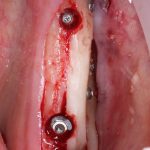

Забор костного фрагмента проводится с наружной косой линии с помощью ультразвукового пьезохирургического инструмента. Ничего сверхнового и супернеобычного тут нет, совершенно стандартная методика. С той лишь разницей, что молоток для этого используют только фашисты и только в гестапо использовать не нужно, всё делается усилием и ловкостью рук.

Нюансы начинаются с обработки принимающего ложа. Да-да, уважаемые друзья, одна из причин некроза блоков, их чрезмерной атрофии и прочих проблем — в отсутствии обработки принимающего ложа. Некоторые делают дырки, но правильнее и эффективнее поступить так:

то есть, просто снять слой кортикальной пластинки с участка, к которому будет фиксироваться костный блок. Почему? Читайте здесь>>.

Вторая особенность — мы не адаптируем и не обрабатываем костный блок invitro, а фиксируем его так, как есть:

после чего обрабатываем — доводим до окончательной формы альвеолярного гребня: